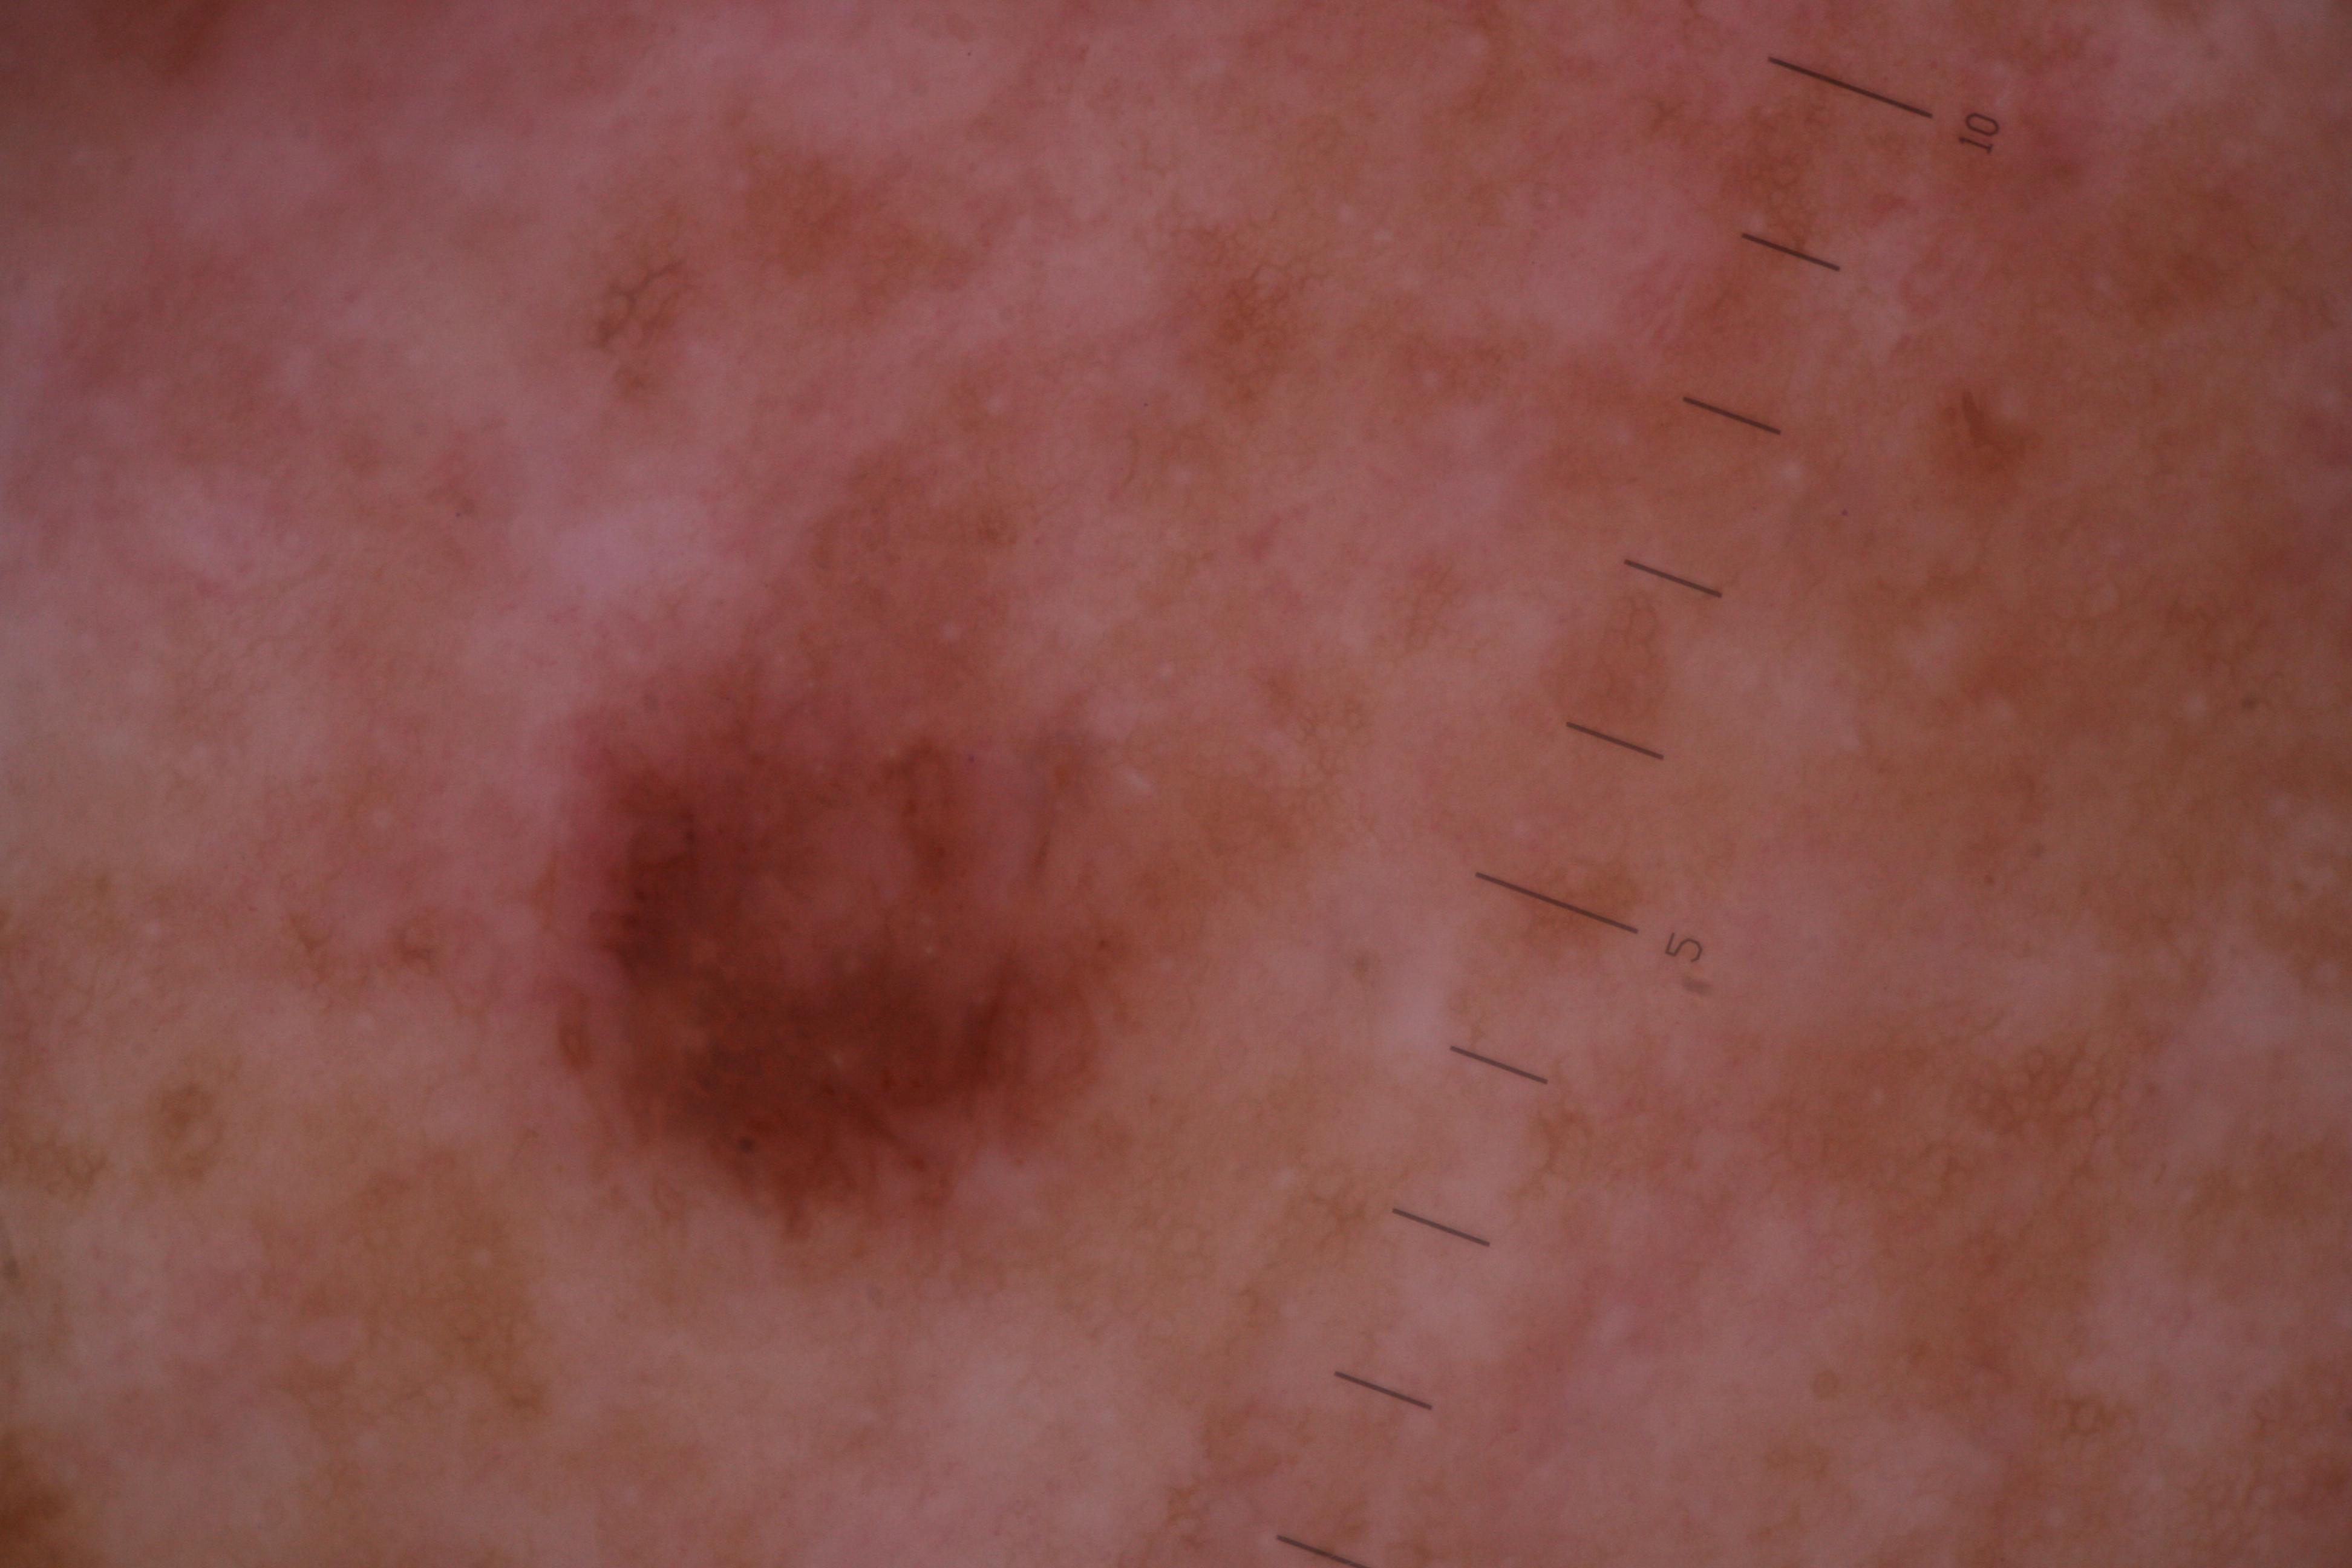

ISIC_6742970

- Sydney Melanoma Diagnostic Center at Royal Prince Alfred Hospital, Pascale Guitera

- Challenge 2020: Training

Clinical

| Field | Value |

|---|---|

| acquisition_day | 91 |

| age_approx | 75 |

| anatom_site_1 | Trunk |

| anatom_site_2 | Posterior trunk |

| concomitant_biopsy | False |

| diagnosis_1 | Benign |

| diagnosis_confirm_type | serial imaging showing no change |

| fitzpatrick_skin_type | I |

| image_type | dermoscopic |

| lesion_id | IL_7403129 |

| patient_id | IP_4261345 |

| sex | male |